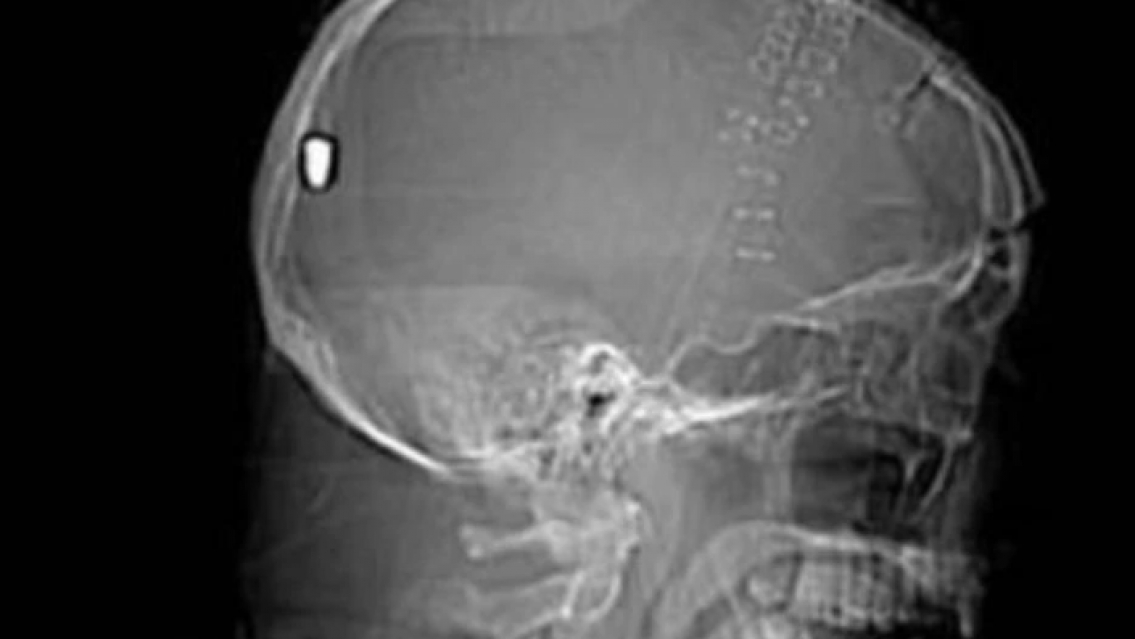

Le hicieron una tomografía por un golpe y le descubrieron el proyectil.

Un siniestro vial protagonizado por un hombre en el barrio La Merced de San Pedro de Jujuy, terminó en un misterio para los médicos que lo atendieron en el hospital "Guillermo Páterson", que tras realizarle una tomografía descubrieron que el sujeto tenía una bala alojada en su cabeza.

Los profesionales de la salud se llevaron una gran sorpresa, ya que en las imágenes se observaba un proyectil, aunque en la cabeza no se encontró ninguna herida que denote por donde había ingresado a esta zona.